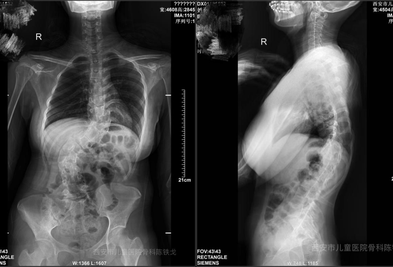

西安市儿童医院攻克高难度手术 助17岁重度脊柱畸形少年重获挺拔人生 近日,西安市儿童医院骨科团队凭借精湛医术与多学科协作,成功为一名17岁重度先天性脊柱畸形患儿完成高难度矫形手术,不仅矫正了严重扭曲的脊柱,更让少年重燃生活希望,标志着该院在复杂脊柱外科领域取得新突破。 2周前